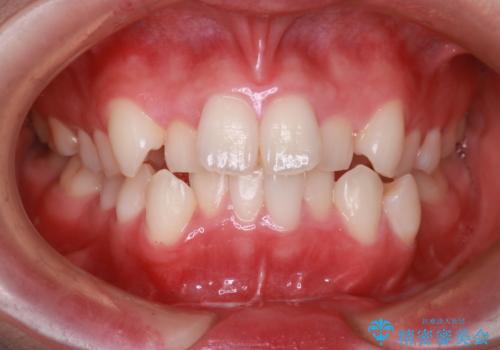

【抜歯インビザ】前歯の凸凹をなおしたい

- 前歯の凸凹を主訴に来院されました。

前歯はあまり下げる必要がなかったため、上下左右の第二小臼歯抜歯を行う治療計画としました。

途中、臼歯の近心傾斜を認めましたが、追加アライナーを使用することでリカバリーを行いながらインビザラインのみで治療を完了することができました。